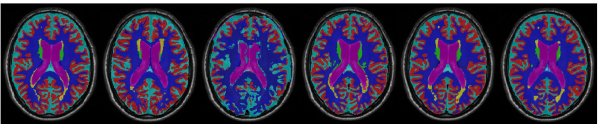

Ground truth ANTs-1 [15] Aug. + U-Net-1 [26] MRE-Net-1 (ours) Aug. + U-Net-6 [26] Aug. + U-Net-20 [26]

Regarding the few-shot setting, we can observe apparent improvements in both Dice and HD95 by increasing the number of training samples from one to three. Notably, using two training samples, our MRE-Net already exceeded U-Net-6 in terms of mean HD95; when using three training samples, the MRE-Net achieved a mean Dice higher than that of U-Net-6. In summary, the MRE-Net achieved the best performance in both the one- and few-shot settings, demonstrating competence in low-shot brain MRI segmentation. Example segmentation results of different methods are shown in Fig. 3.